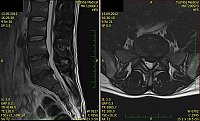

1. Žena, 48 let. Na MR patrná 8mm velká paramediální hernie L5/S1 vlevo s extruzí materiálu ploténky do epidurálního prostoru a útlakem kořenů L5 a S1 vlevo. Pacientce byla doporučena operace, kterou odmítla a zvolila alternativní postup s aplikací ozonu. Viz obr. 6a

Na kontrolním MR po 1 měsíci (po 2 aplikacích ozonu) periradikulárně je viditelné vymizení fragmentů v epidurálním prostoru a částečná retrakce meziobratlové ploténky. Subjektivně výrazná úleva, po 4 týdnech návrat do práce. Viz obr. 6b